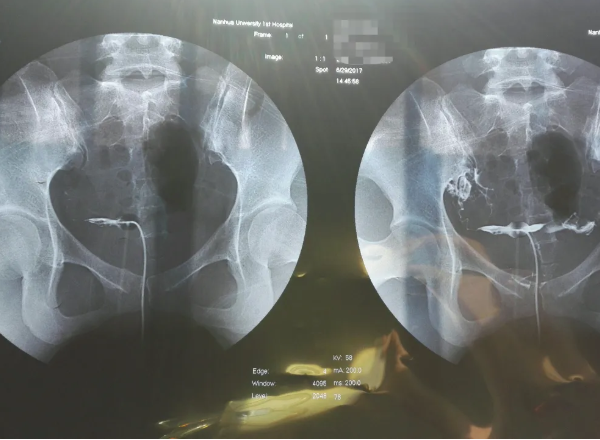

輸卵管造影對子宮會有一定傷害,但傷害幾乎可以忽略不計。因為輸卵管造影是侵入性檢查,不像超聲一樣方便。需要把造影管放入患者的子宮腔內,然後再打造影劑,接著在超聲下或X線下監測造影劑的彌散情況。在操作過程中,容易誘發逆行感染,同時造影劑進入子宮腔內對子宮內膜也會有一定損傷。